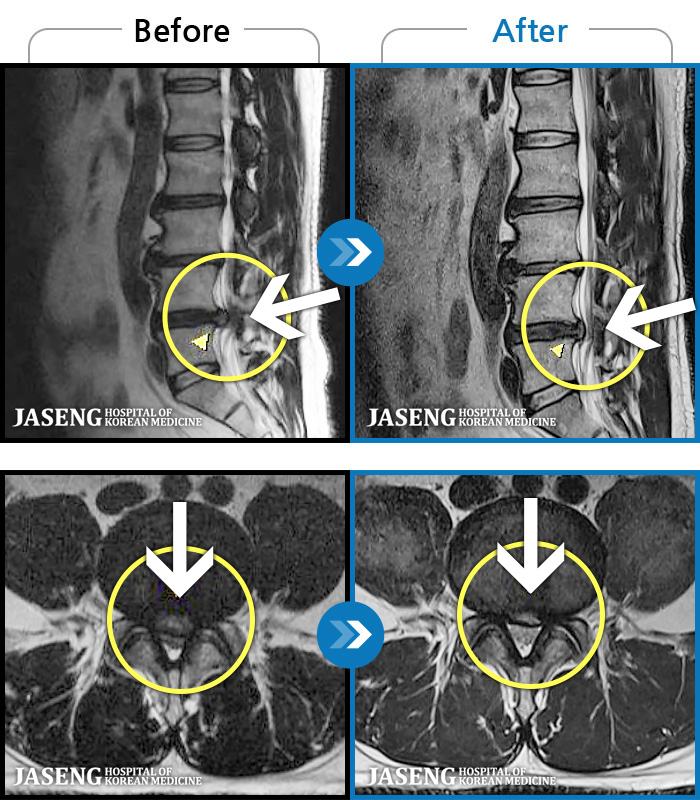

[뱸] 19.11.28~25.05.06